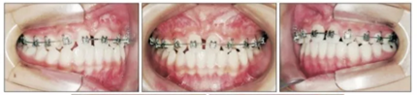

第二階段(圖5,6;表2)

面弓矯治包括在混合牙列及早期恒牙列的傳統(tǒng)牙支抗面弓及恒牙列的骨支抗面弓。由于患者曾行腭成形術(shù),為了將矯治力傳遞到上頜骨,使用唇舌弓而不是快擴(kuò)。8歲5月時(shí)開始用面弓聯(lián)合唇舌弓矯治(500g/邊,與合平面呈30°向下),持續(xù)3年6月?;颊吲宕鲿r(shí)間為12-14時(shí)/天。

上頜前磨牙萌出后取出唇舌弓,上固定矯治器以排齊上頜牙列,該階段面弓暫時(shí)停止使用。